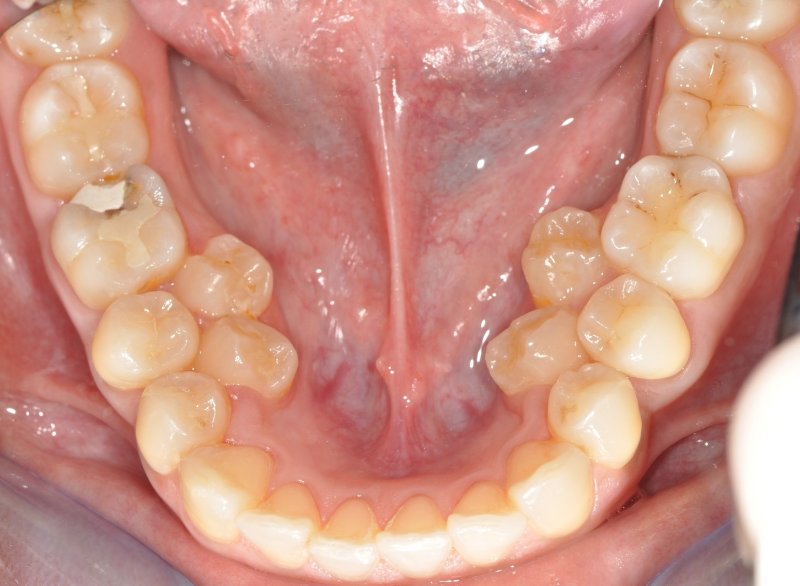

Hyperdontia: the presence of extra (supernumerary) teeth.

Below are examples of mild cases, and examples of extreme cases.

MILD CASES

Hyperdontia is the condition of having supernumerary teeth, or teeth that appear in addition to the regular number of teeth. They can appear in any area of the dental arch and can affect any dental organ.

There is evidence of hereditary factors along with some evidence of environmental factors leading to this condition. While a single excess tooth is relatively common, multiple hyperdontia is rare in people with no other associated diseases or syndromes. Many supernumerary teeth never erupt, but they may delay eruption of nearby teeth or cause other dental or orthodontic problems. Molar-type extra teeth are the rarest form. Dental x-rays are often used to diagnose hyperdontia.